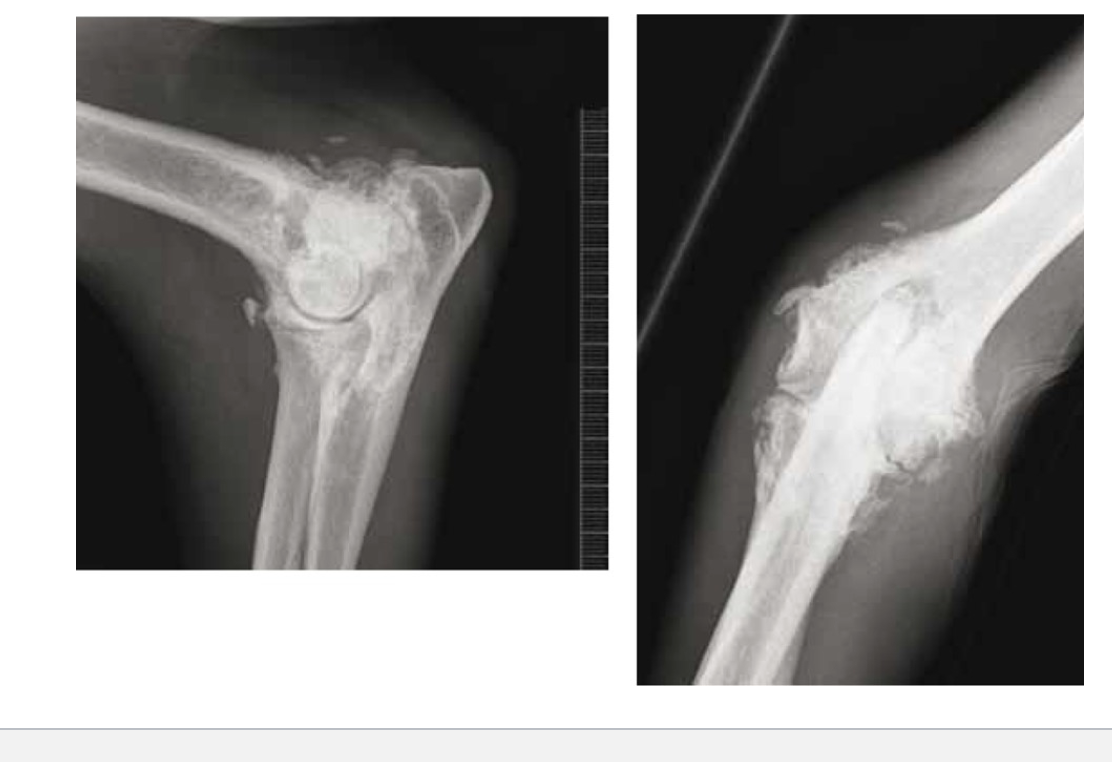

OSA diagnosis

Radiographs of bone

Radiographs of the chest

Bone biopsy

Osteosarcoma

Most common type of primary bone tumor

Can result in secondary mastasis

Common in large/ giant breeds

75% occur in appendicular skeleton